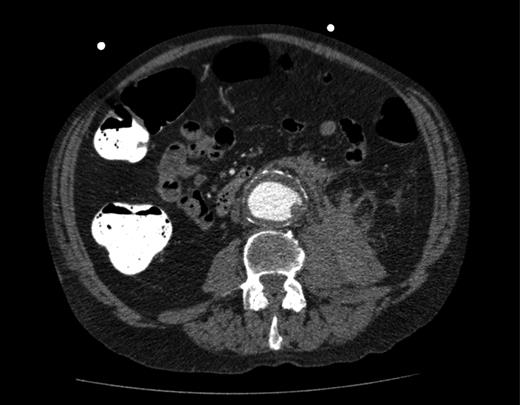

A computed tomography (CT) of the abdomen and pelvis was performed. This showed a grossly distended urinary bladder and compression of the sigmoid colon against the sacral promontory causing bowel obstruction (Figs 1 and 2, respectively) as well as a 4.9 cm abdominal aortic aneurysm without any signs of a rupture (Fig. 3). The plan was to consult our vascular colleagues regarding management of the AAA once the obstruction had settled.

Further image of the same CT scan showing compression of the sigmoid colon against the sacral promontory (see arrow) behind the distended bladder.